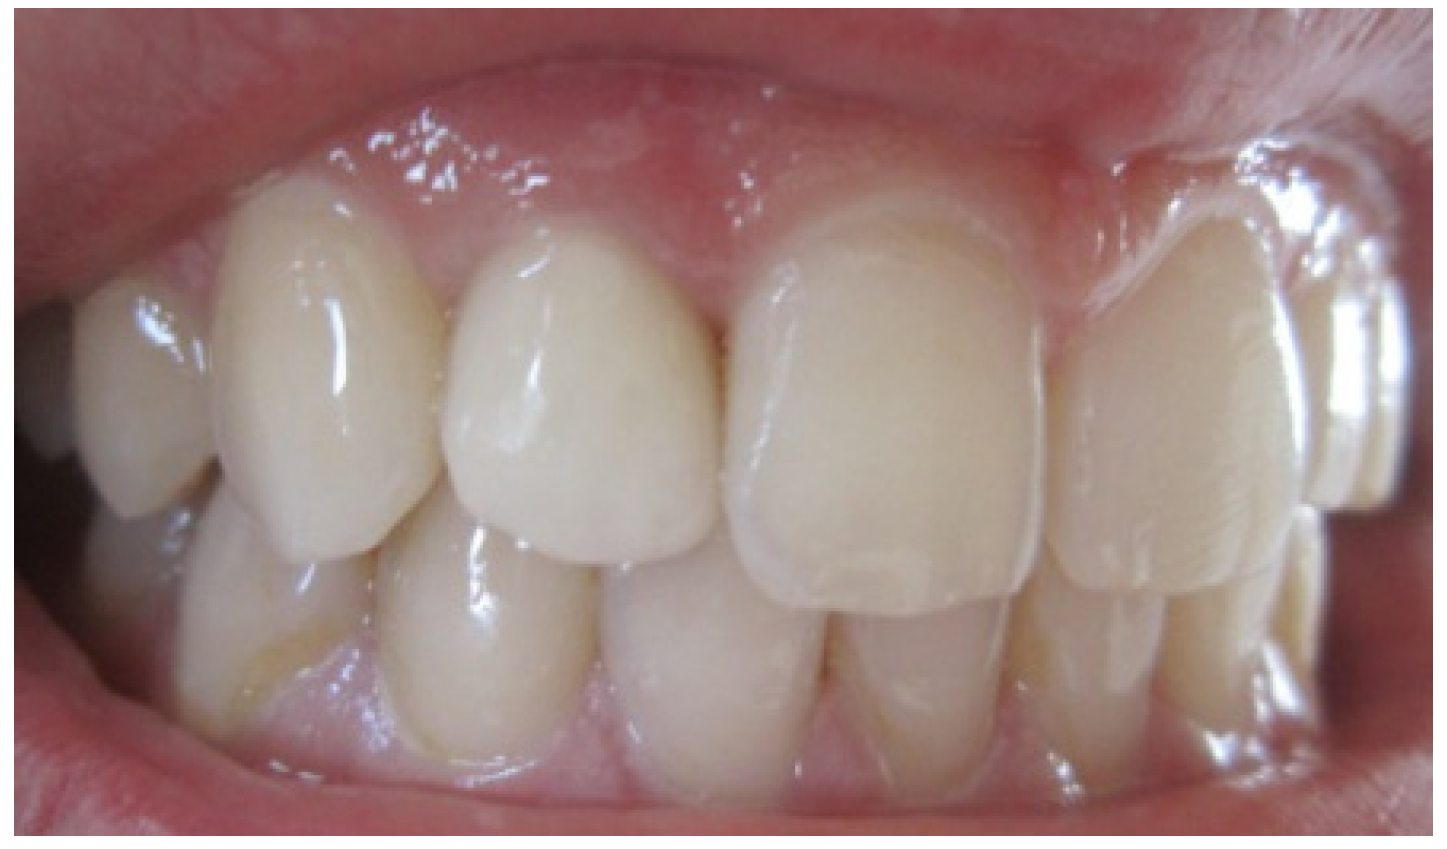

Aesthetic assessment showed a squared teeth form, a size discrepancy and a non-symmetrical gingival architecture between the left and right lateral incisors (Figure 2). A slight asymmetry between the gingival margins of the right and left central incisors was noticeable. However, the patient did not express her dissatisfaction about it and refused any surgery on her sound teeth.

Figure 2. Gingival display due to the asymmetrical ZENITH.

After 4 months of maturation, the abutment tooth was refined after placement and buildup of post and core materials (Figure 6). Later, a full arch impression was taken using a silicone material. An impression of the opposing dentition was also made with irreversible hydrocolloid. The shade was determined with the shade guide (VITA). The final restoration, Zirconia based crown, showing natural appearance with a correct gingival architecture was performed using the CAD/CAM technology. All of the team, including the prosthodontist, periodontist and the ceramist, were satisfied by the result—an aesthetic and functional restoration with a good marginal adaptation and an improved pink and white score (Figure 7). The most grateful of all was, however, our satisfied patient.

Figure 7. Final result showing an improvement of aesthetic appearance.